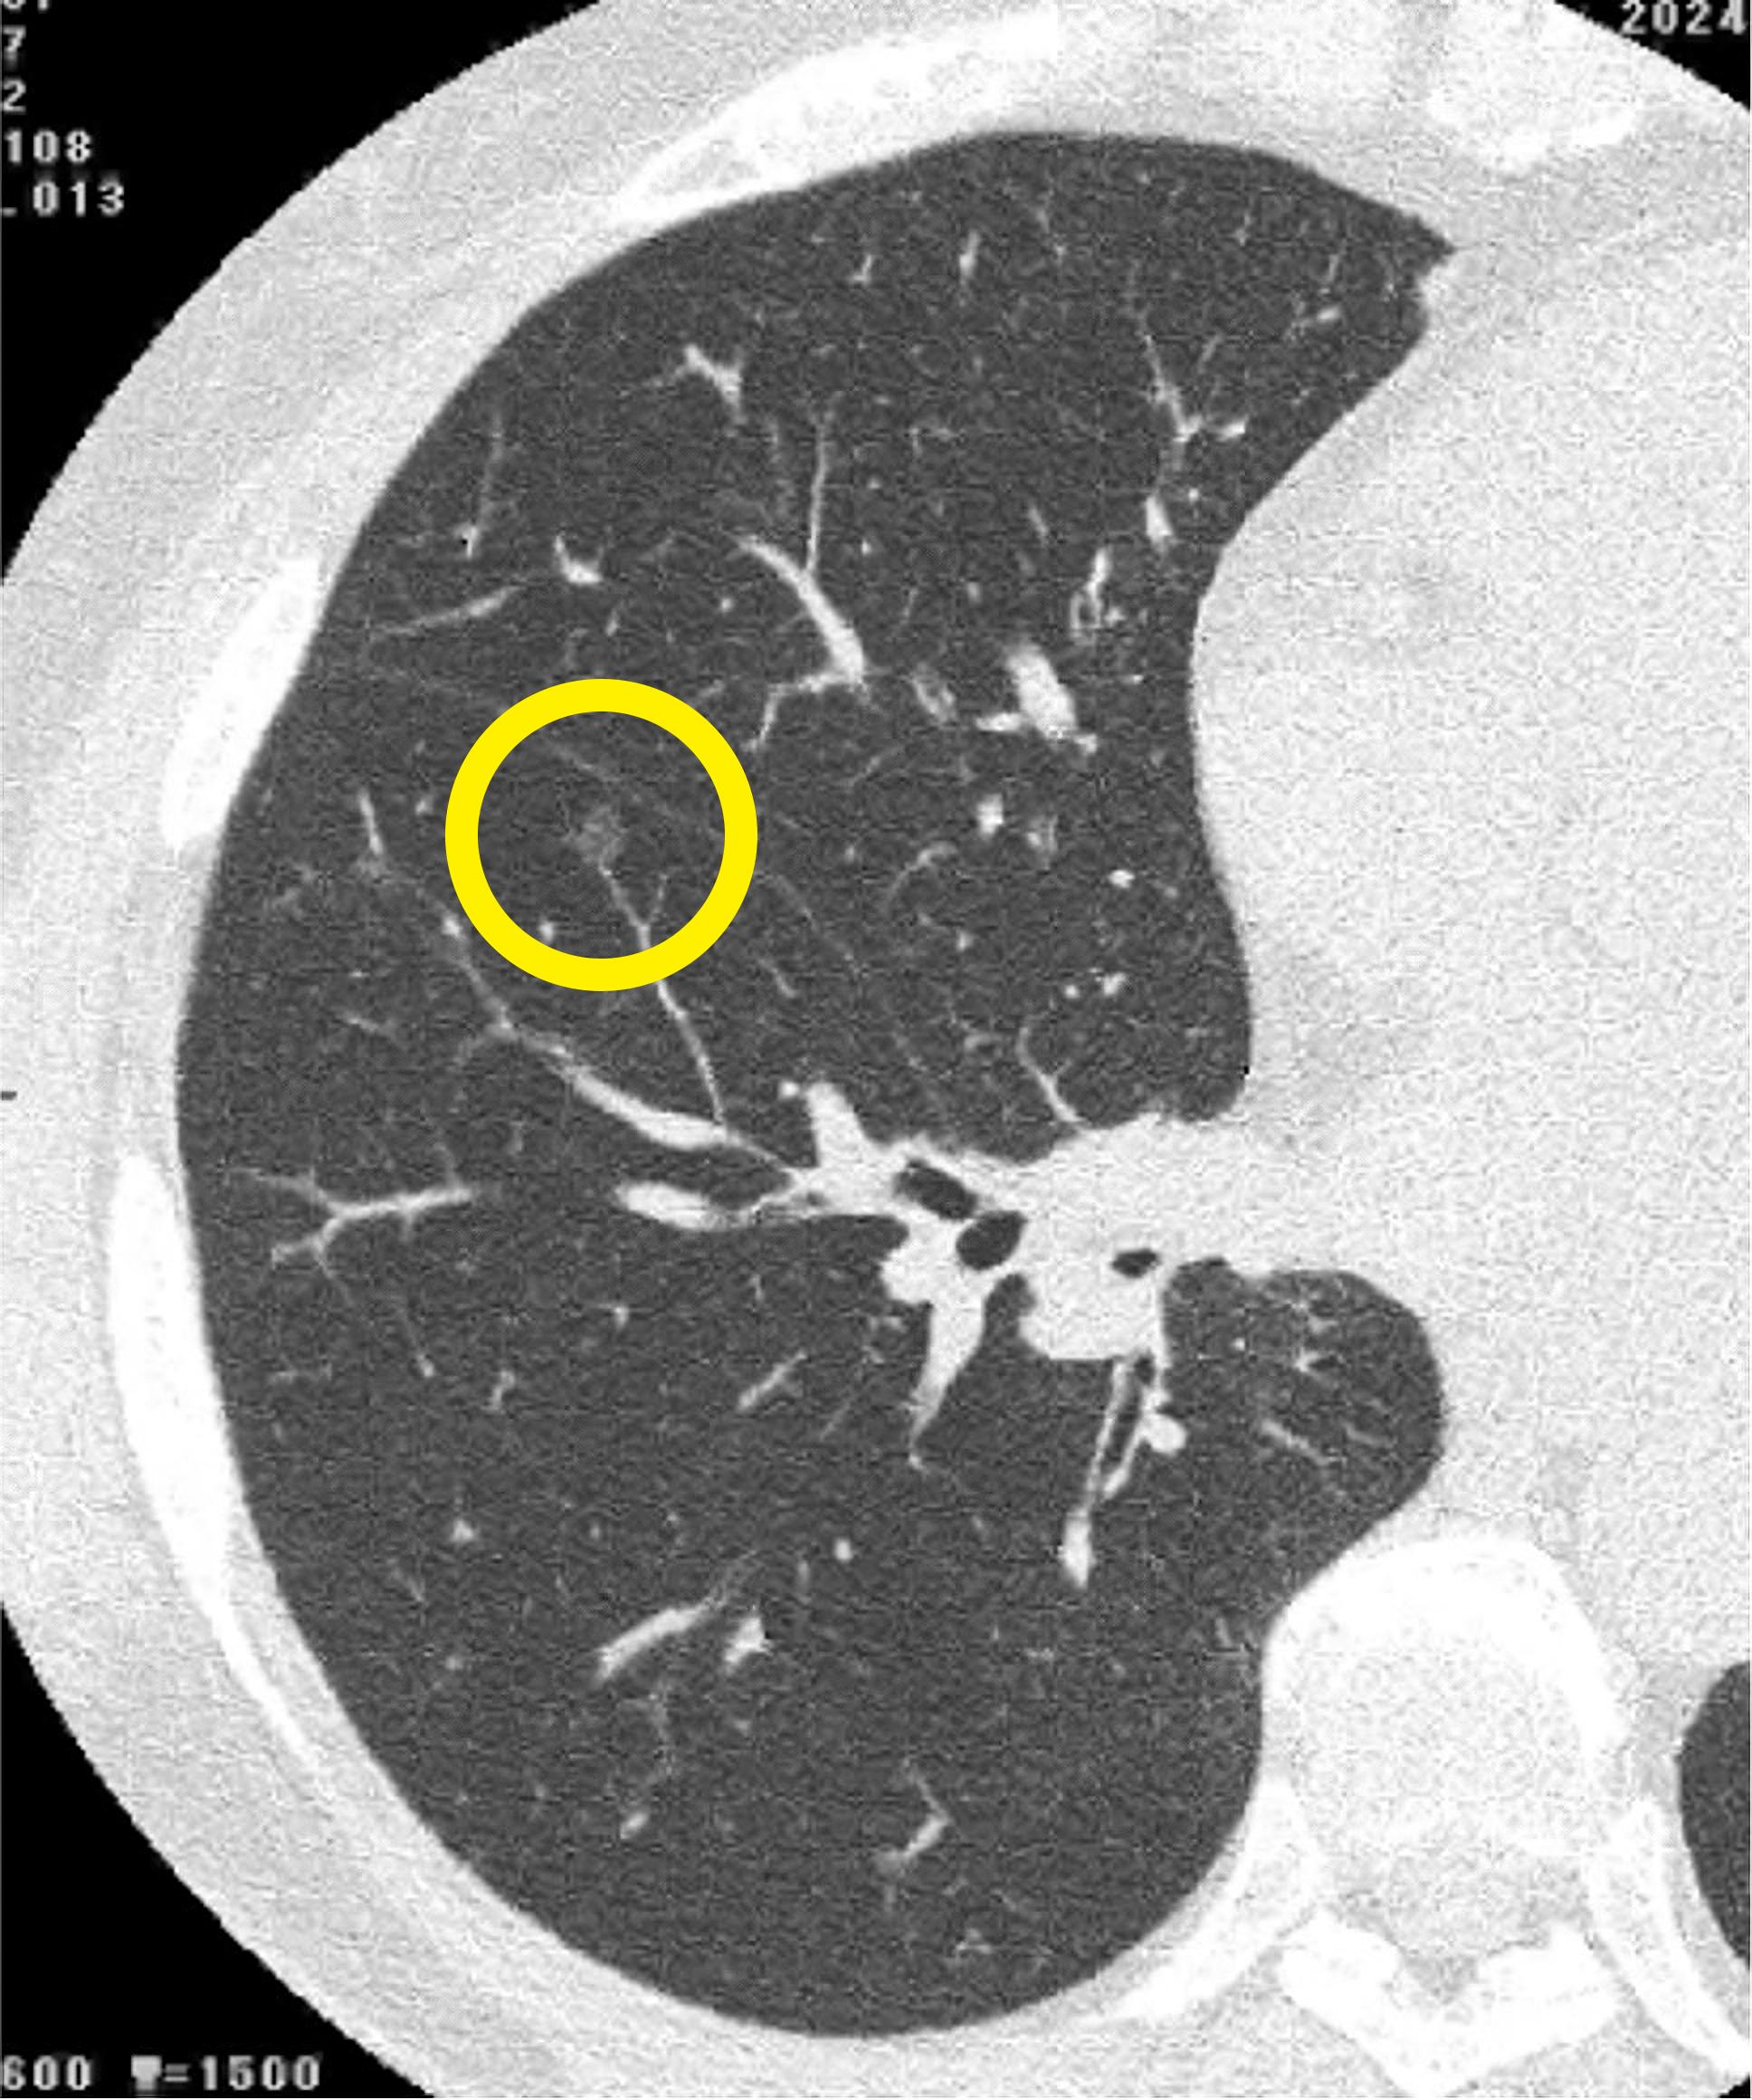

マイシグナル・スキャンを受けて肺がんのリスクが検出された60代のお客さま。精密検査を経て、北海道大学病院呼吸器外科で該当腫瘍を切除する手術を実施し、無事にステージ0の肺がんを取り除くことができました。

レントゲンでは通常映らない、4mm程度の超早期がんのCT画像

マイシグナル・スキャンを受けて肺がんのリスクが検出された60代のお客さま。

精密検査を経て、北海道大学病院呼吸器外科で該当腫瘍を切除する手術を実施し、無事にステージ0の肺がんを取り除くことができました。